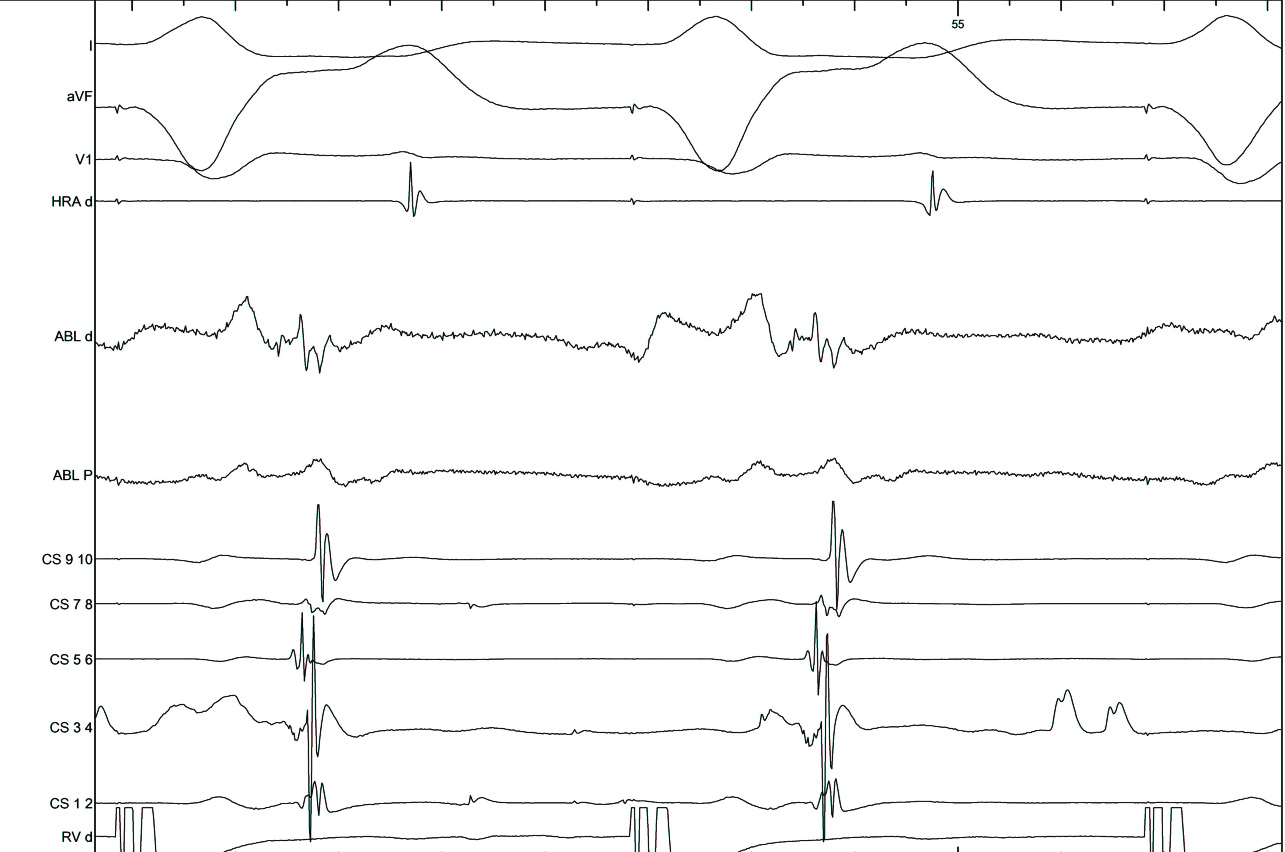

#5 Mapping in diverticulum - CSE potential most important

diverticulum.jpg

med_lat.jpg

signals.jpg